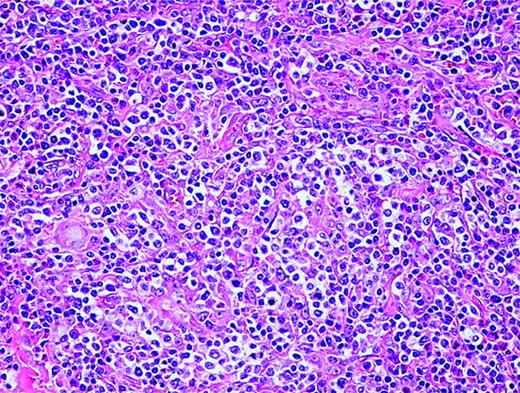

AITL is characterized by a polymorphous infiltrate of lymph nodes with the normal nodal architecture commonly effaced with opened and dilated peripheral sinuses. There is often significant proliferation of high endothelial venules and follicular dendritic cells (Figure 2). The lymphoid cells commonly consist of a mixture of small and medium-sized lymphocytes with plasma cells and B-immunoblasts, while clusters of epithelioid histiocytes and many eosinophils may be present. T-cell-associated antigens are usually expressed, with CD4 expression more common than CD8 expression.

Angioimmunoblastic T-cell lymphoma. Many small vessels (high endothelial venules), histiocytes, scattered eosinophils, and plasma cells are admixed with the tumor cells that display clear cytoplasm.